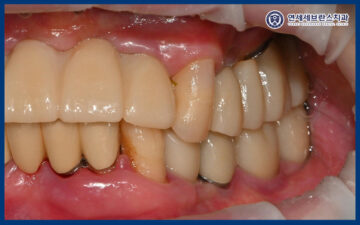

25.06.21 / 25.07.19

이렇게 임플란트의 치유기간을 거쳐

잇몸뼈와 잘 결합되어

최종 보철 작업을 시작하였습니다.

25.07.19

그리고 맞춤형 지대주에 맞는

최종 보철을 제작하여

맞춰보았습니다.

보철물의 형태와 색상,

교합 상태를 꼼꼼하게 확인한 뒤

불편한 부분은 없는지 점검하며

세밀한 조정을 시행하였습니다.